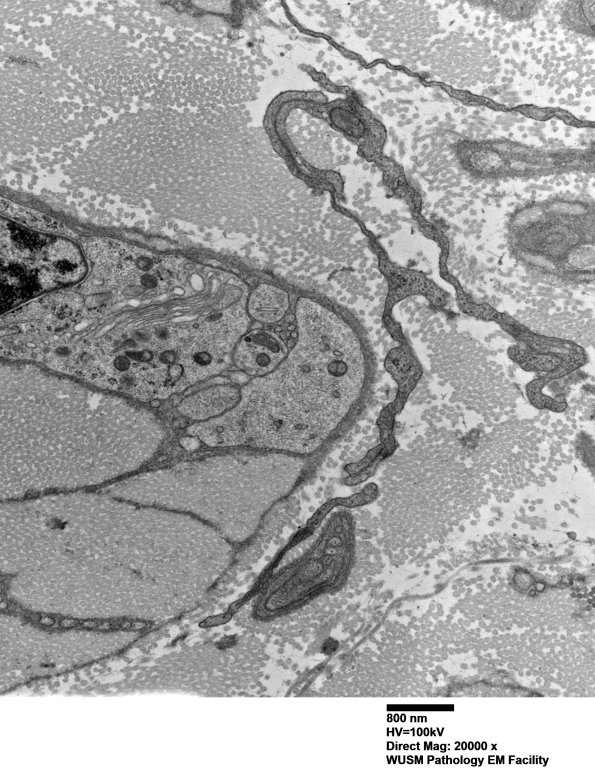

7A3E-G At the right edge of the Schwann cell shown in 7A3A are a variety of delicate processes that appear to be fibroblastic and/or Schwann cell derived. (electron micrographs)